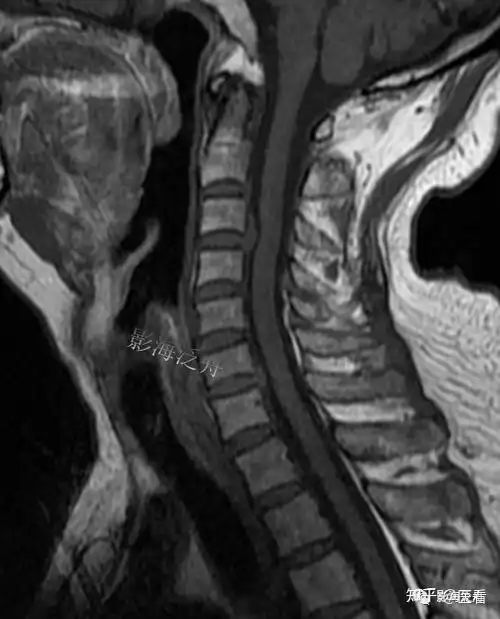

典型病例颈椎后纵韧带钙化mr